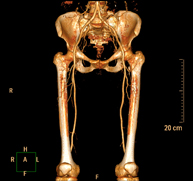

Prova diagnòstica no invasiva que consisteix en l'estudi vascular del sector aorto-ilíac i dels vasos arterials d'ambdues extremitats inferiors i l'obtenció d'imatges d'alta definició anatòmica mitjançant l'ús d'un equip de TC Multidetector d'última generació i de contrast iodat. La qualitat de les imatges permet realitzar reconstruccions en 2D i 3D gràcies a estacions de treball especialitzades en l'estudi arterial.

Prova diagnòstica no invasiva que consisteix en l'estudi de vascular del sector aorto-ílíac i dels vasos arterials d'ambdues extremitats inferiors amb l'obtenció d'imatges d'alta definició anatòmica mitjançant l'ús d'un equip de TC (Tomografia Computaritzada) i contrast iodat. La qualitat de les imatges permet realitzar reconstruccions en 2D i 3D gràcies a estacions de treball especialitzades en l'estudi arterial.